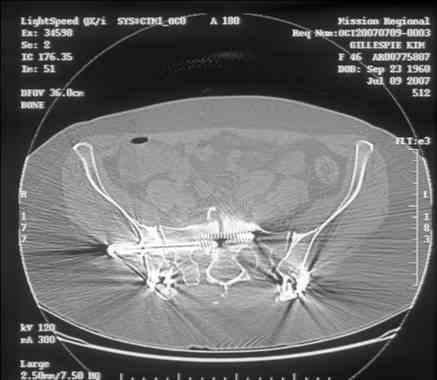

Here is a magnified view. Sorry about the quality but the CT was scanned into our system.

Thank you...it might help to remove the disengaged and other iliosacral screws then insert longer lag screws into the upper sacral segment and if anatomically feasible into the second sacral segment as well.

You could do it percutaneously and even add an electrical stimulation device if that seems reasonable.

At this point, I'd ignore the right pubic root issue if asymptomatic.

If simple measures such as those above fail, then you could remove it all, take down the sacral fracture site, refix with alternate techniques, and bone graft.